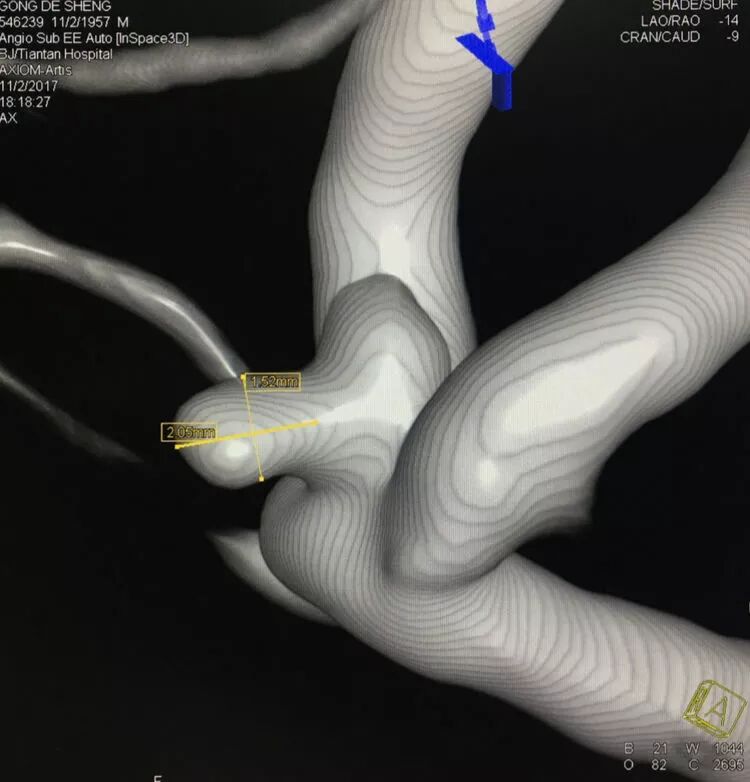

基底动脉顶端宽颈动脉瘤

应用Solitaire支架结合双微管栓塞,一根微导管是45°预塑形的,管头置于瘤体中央(浅管),另一根微导管管头塑成C形,沿瘤底深入到瘤体右侧角(深管)